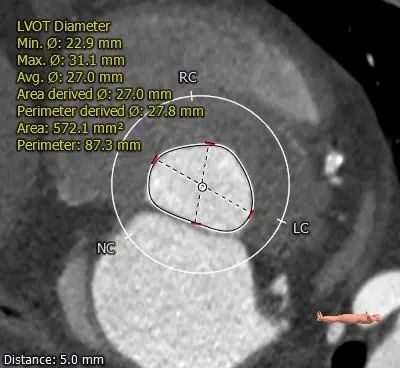

LVOT